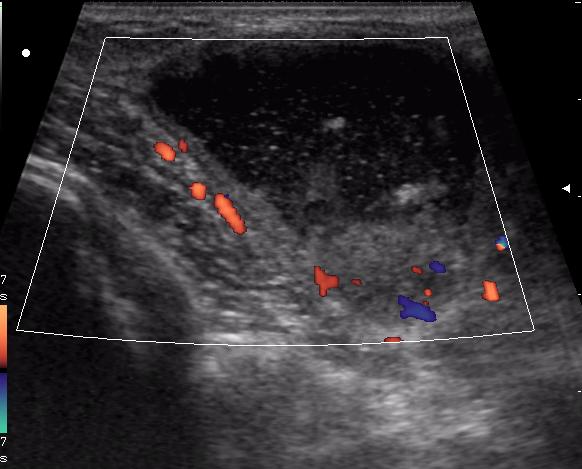

В клинику обратилась мать 11-летней девочки с жалобами на появление припухлости в подключичной области справа. Впервые заметили в феврале. За 4 месяца не интенсивный рост образования, с переходом на переднюю поверхность плеча, где кожа над ним на ограниченном участке (1.5-2см) имеет багрово-синюшную окраску.

(с д-зом Гематома(?) направлена на УЗИ)

достоверной связи с мышцами не увидела. Но на задней проекции включения определяется солидное образование. это может быть лимфоузел?